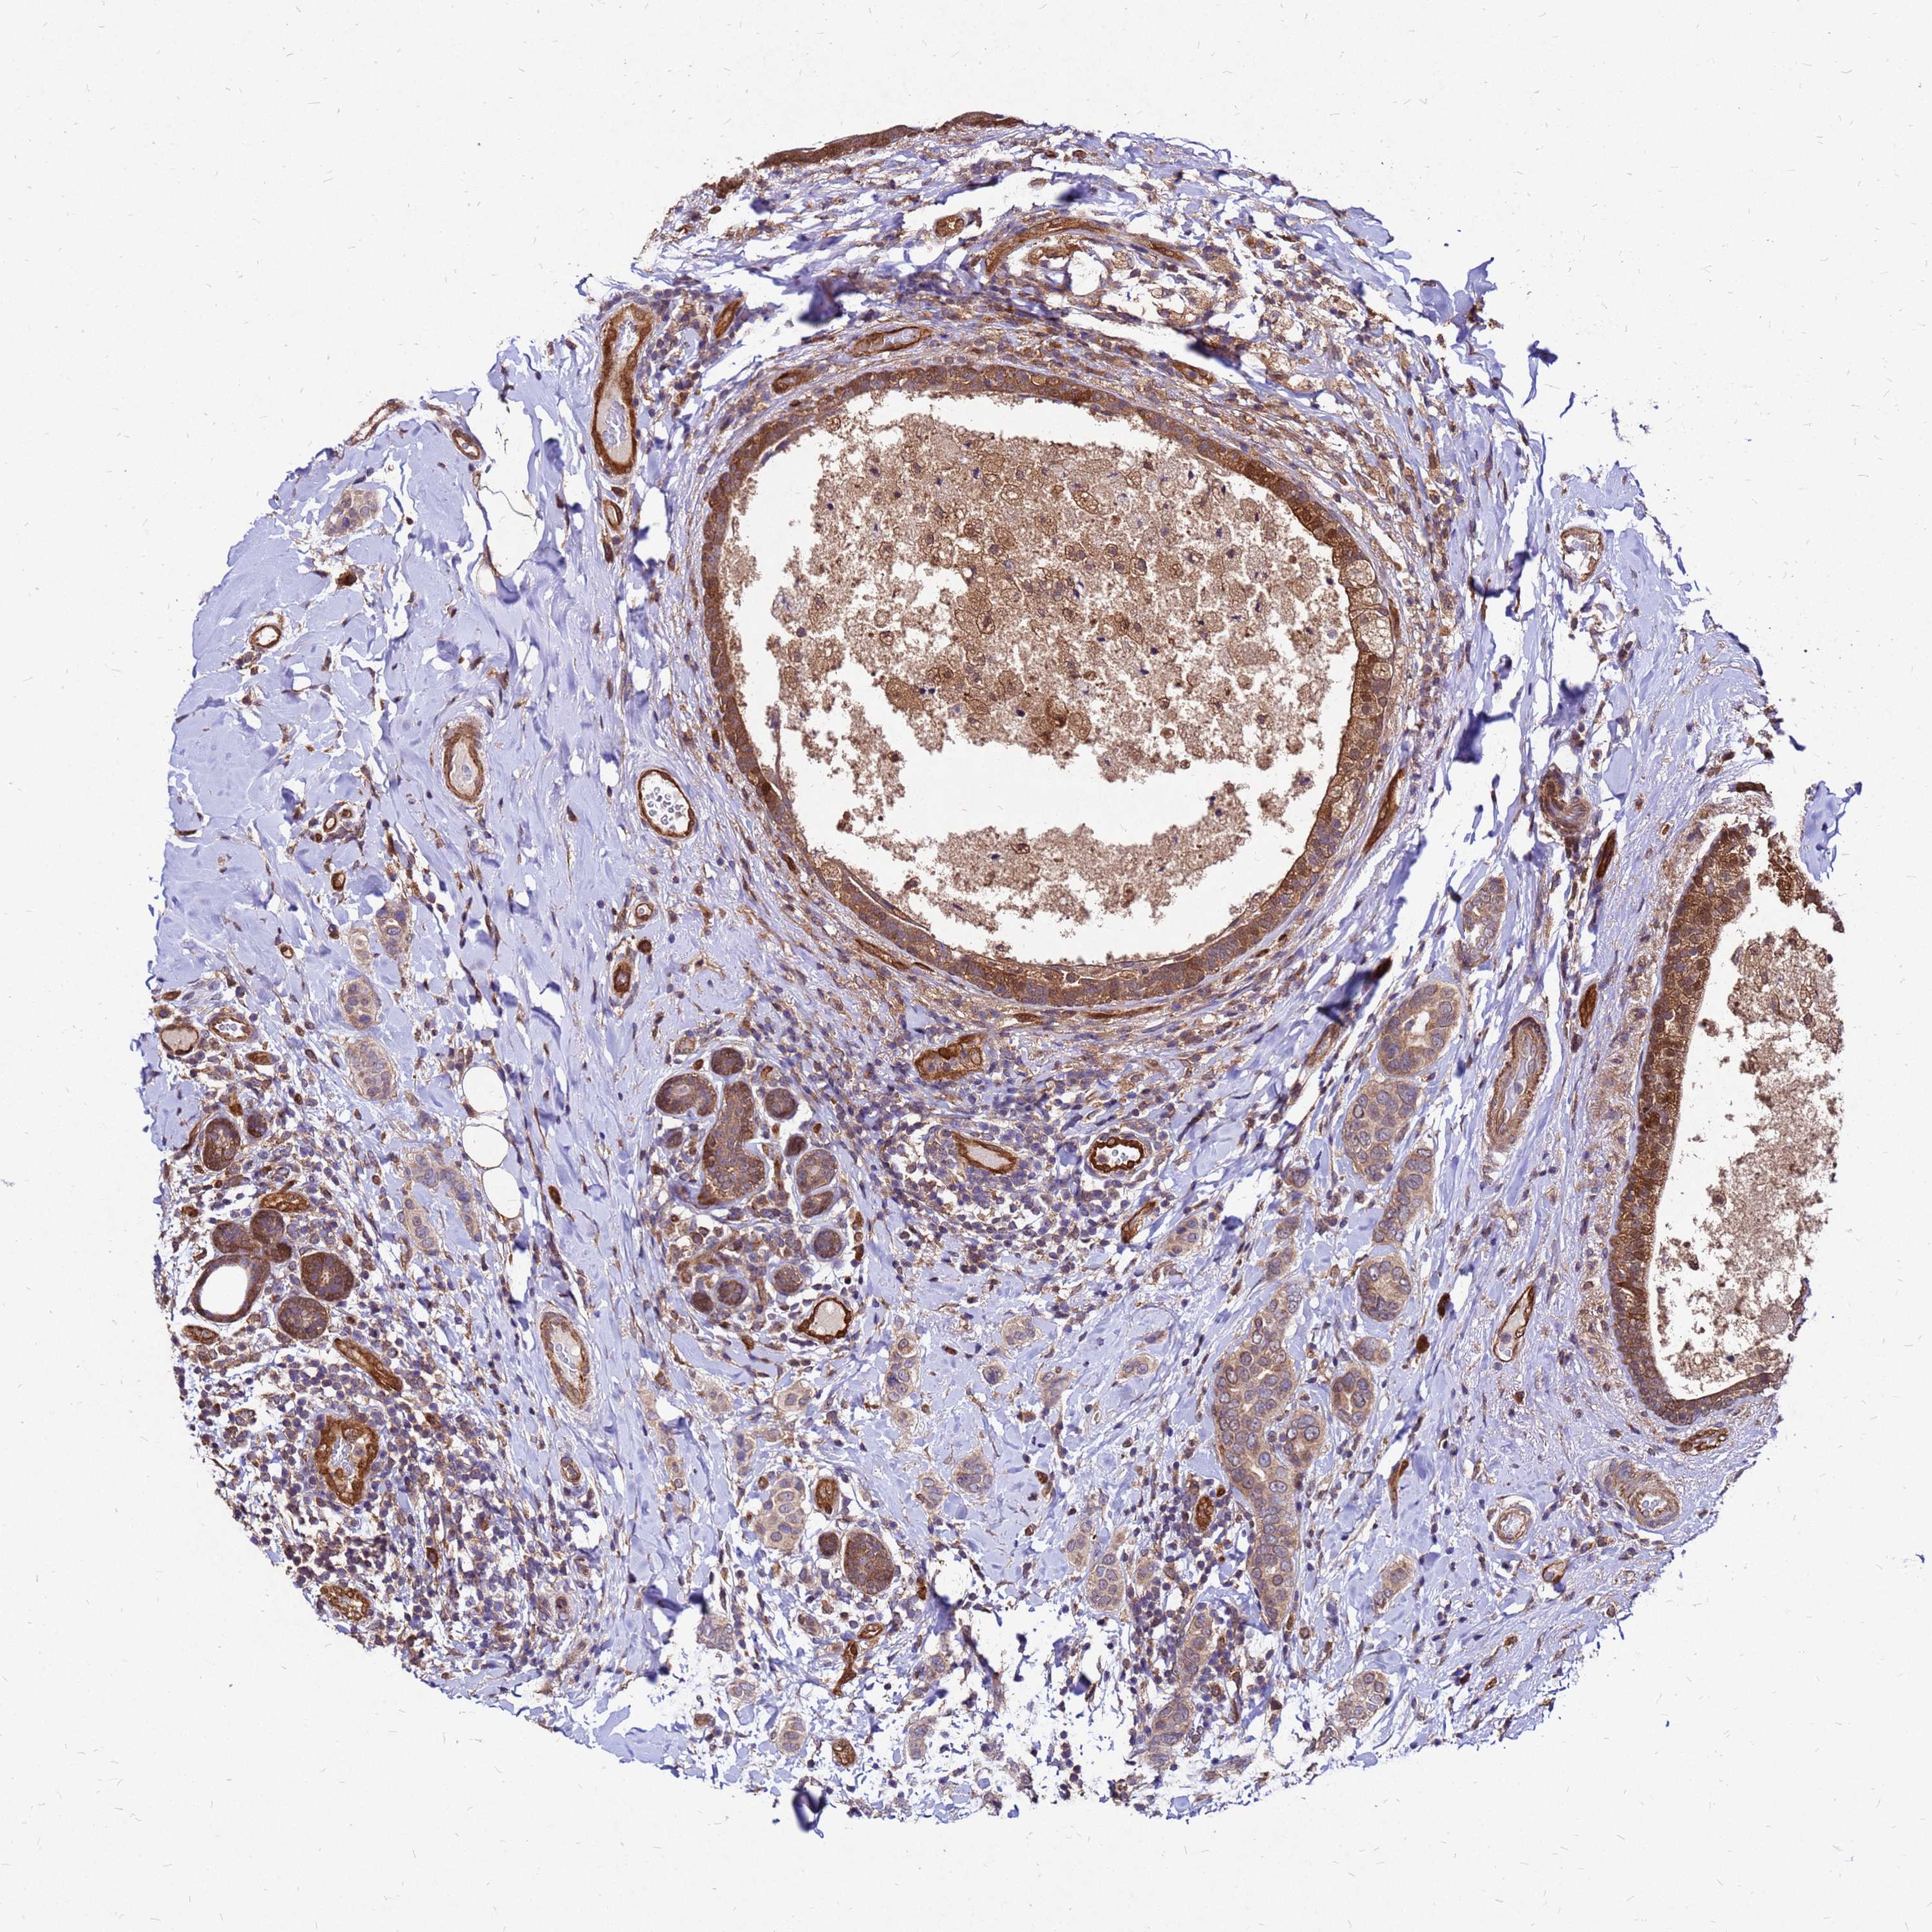

BRCA TCGA BRCA VALIDATION PROTEIN EXPRESSION

ANTIBODIES

AND

VALIDATION